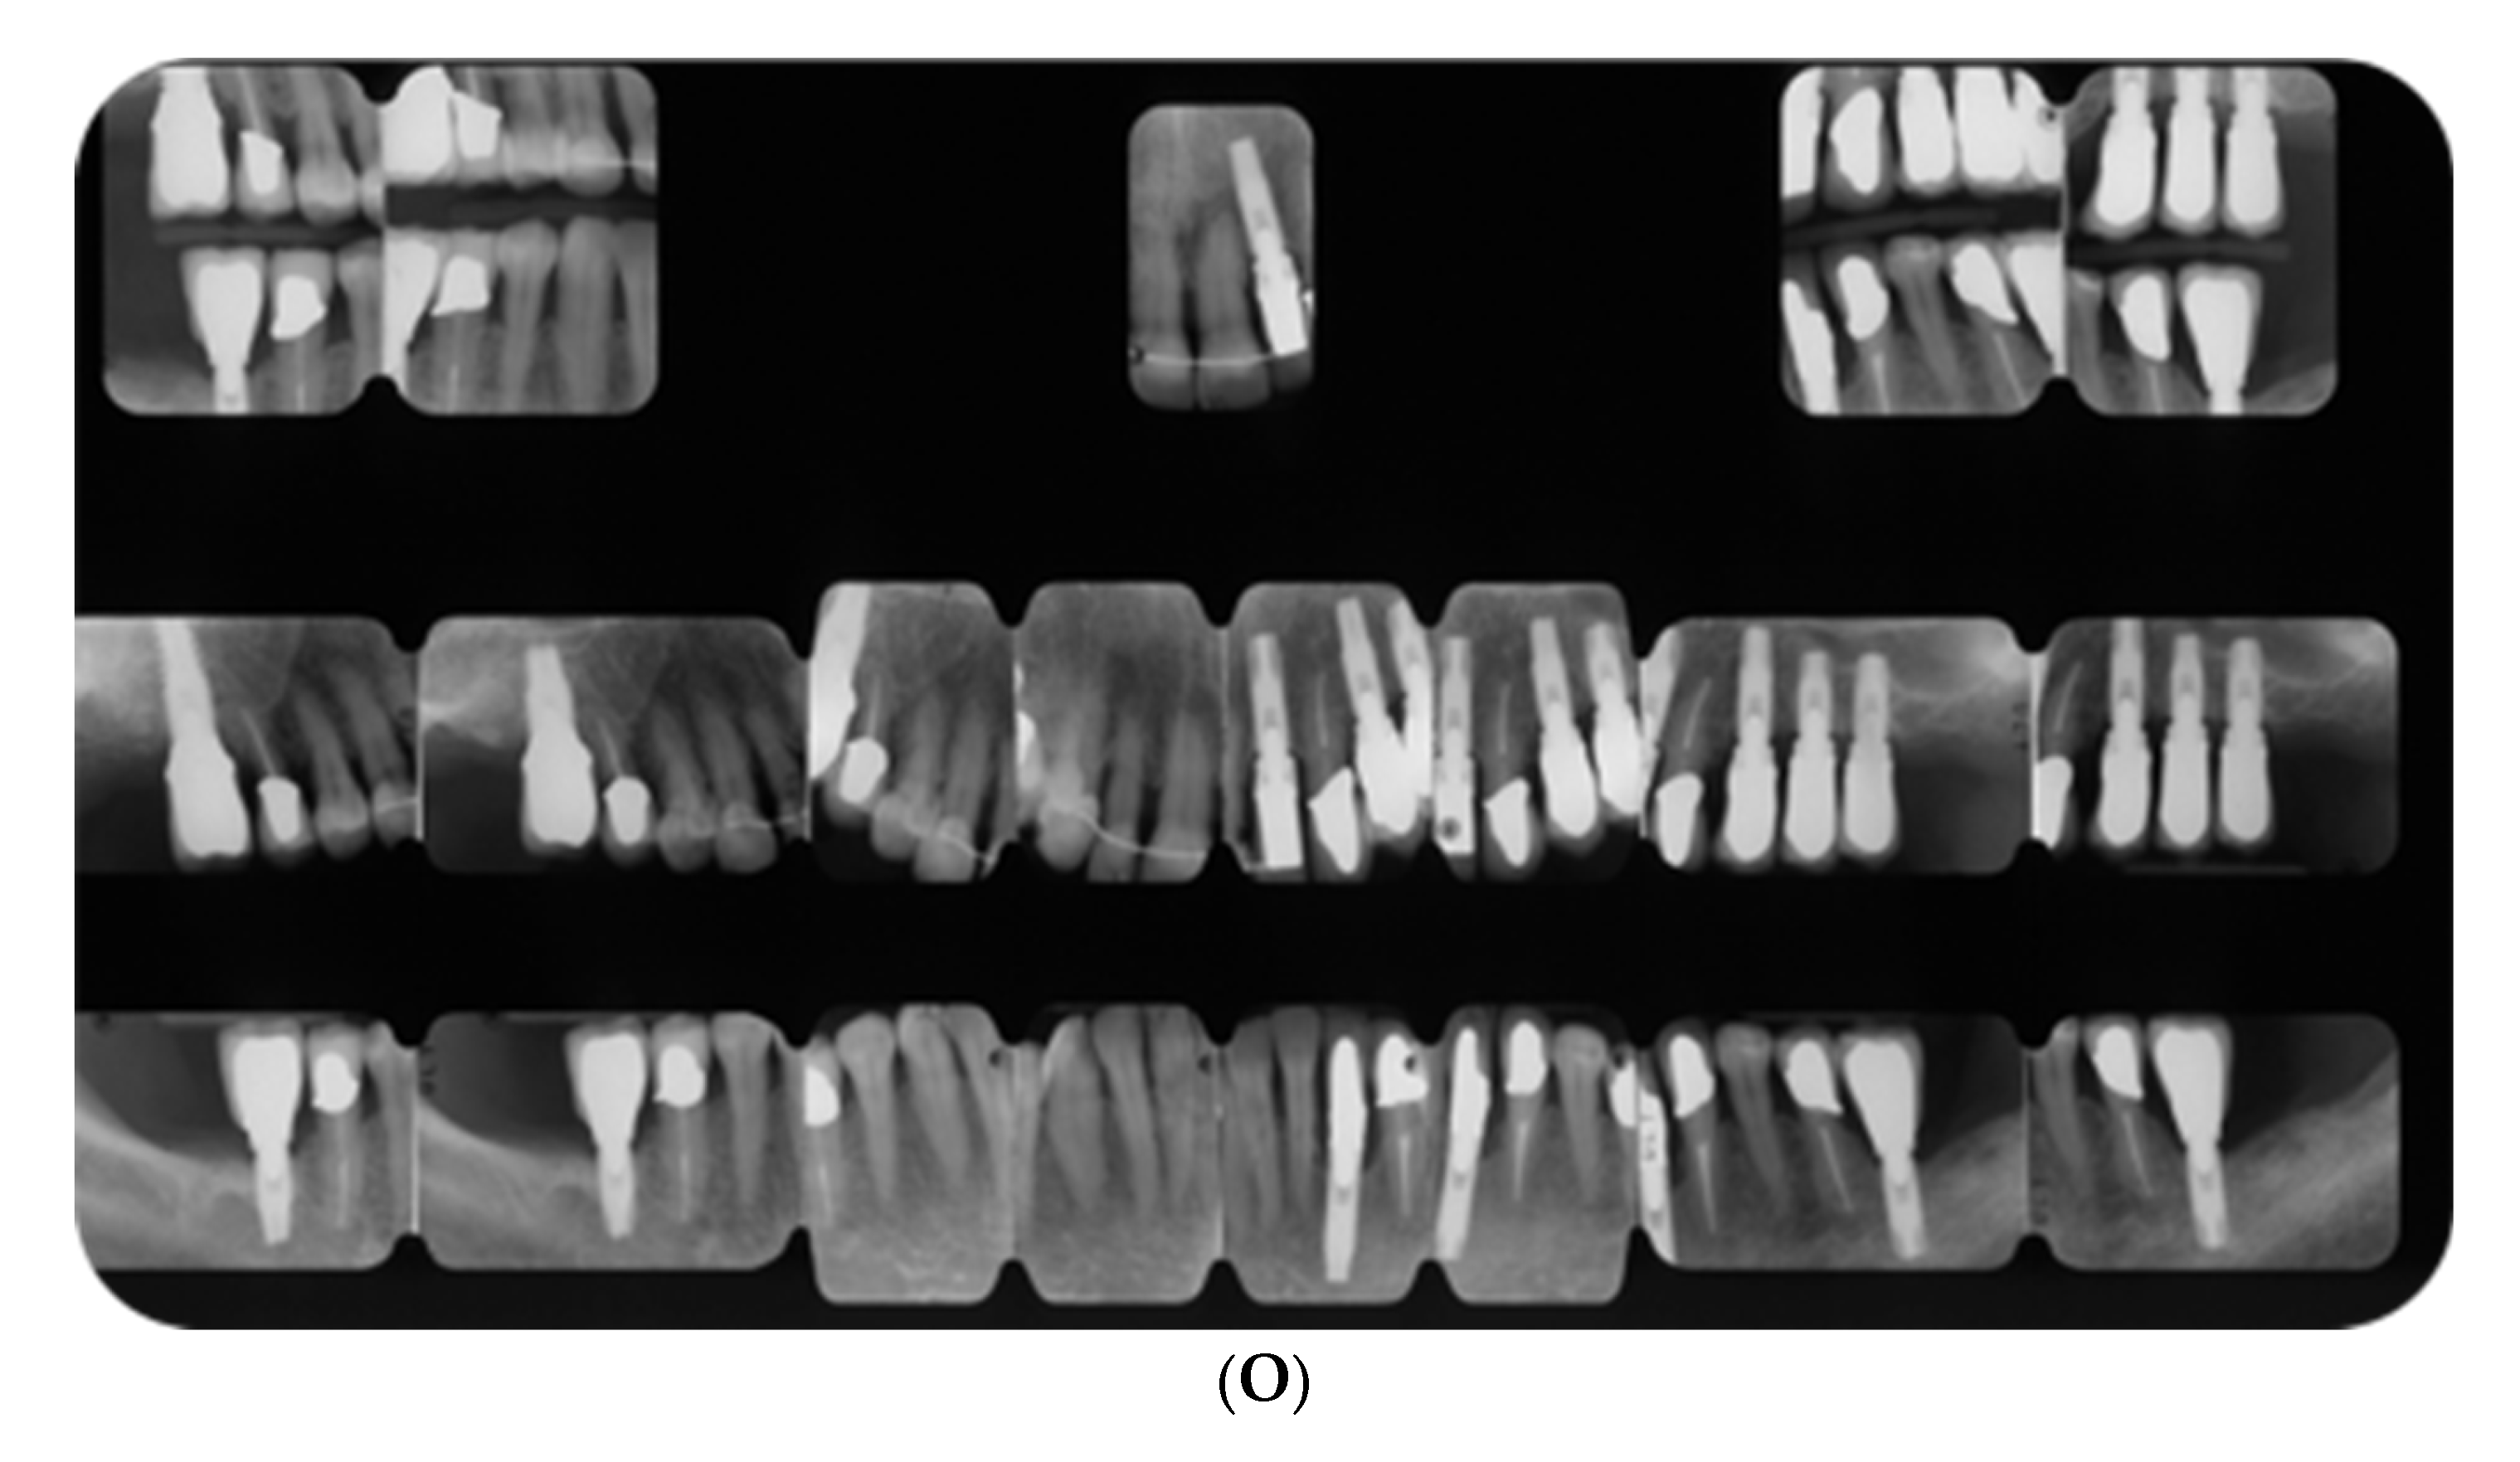

3.3. Periodontal Clinical and Radiographic Outcomes